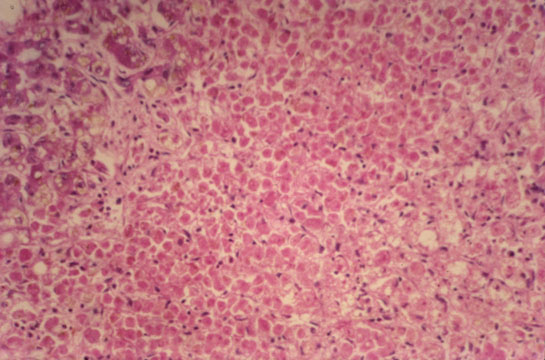

Coagulation necrosis

Fig 28 - COAGULATION NECROSIS: The cells are eosinophilic,moderatly shroncken with angulated borders and pyknotic nuclei.The cells are flat.The change may be reversible.Absent or mild inflammatory reaction.Reticulin is intact.It is the result of ischemia,toxicity, surgical artifacts.The illustration is from a case of acute passive congestion due to acute myocardial infarct.